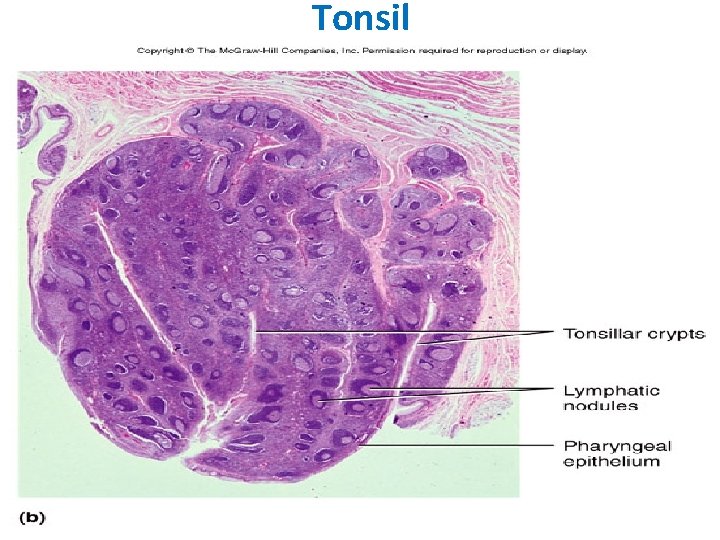

TONSILS These incompletely encapsulated lymphoid aggregates contain many lymphoid nodules; they underlie the mucous membranes (epithelial lining) of the mouth and pharynx. Together with the diffuse subepithelial lymphoid tissue that connects them to form a ring, they guard the common entrance to the digestive and respiratory tracts. The 3 types, palatine tonsils, the pharyngeal tonsil, and lingual tonsils, differ in number, epithelial covering, presence (or absence) and number of epithelial invaginations or crypts, and presence (or absence) of a definitive partial capsule. Most specific structures: epithelial linings, lymphatic nodules under the epithelium with lymphatic infiltration and crypts.

Tonsil